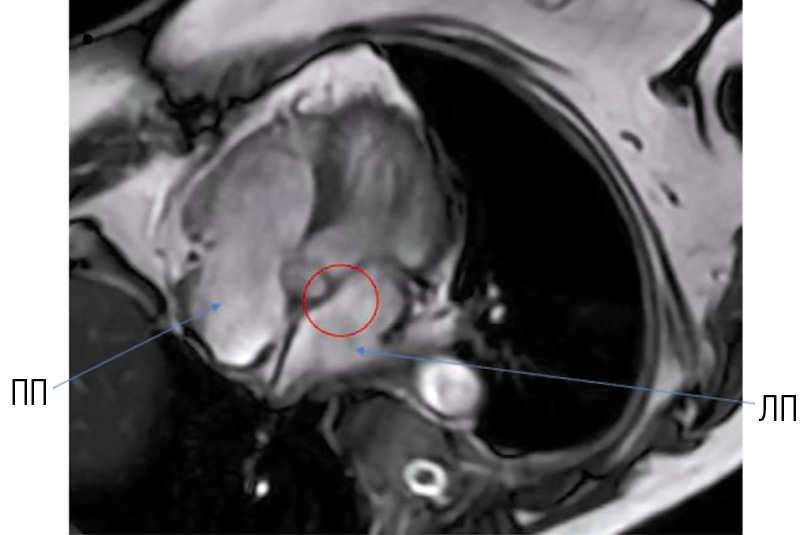

Для окончательной верификации образования в ЛП (тромб / миксома), определения его размеров и выбора дальнейшей тактики лечения была проведена МРТ сердца с гадолинием. По результатам исследования: МР-признаки мелкого образования ЛП, по МР-характеристикам более соответствующего миксоме — мелкое флотирующее образование неправильной формы ориентировочного размера 10×12 мм, фиксированное на уровне средней / нижней трети МПП и направленное в полость ЛП (рис. 2). Образование состоит из «ножки» размером 5×5 мм с изоинтенсивным МР-сигналом на DIR-ИП (импульсная последовательность в режиме Double Inversion Recovery) и гиперинтенсивным — на TIR-ИП (Tau Inversion Recovery), T2 FS-ИП (Fat Suppression), и более «рыхлой» части, слабо дифференцирующейся на киноизображениях и имеющей слабогиперинтенсивный МР-сигнал на TIR-ИП (на рис. 2 — МР-картина постишемического практически трансмурального рубца — нежизнеспособный миокард) в 7-м сегменте передней стенки ЛЖ, наблюдается концентрическая гипертрофия миокарда ЛЖ.

Рис. 3. Короткая ось на уровне предсердий (зелёной линией обведён контур миксомы). / Fig. 3. Short axis is at the level of the atria (myxoma contour is outlined in green).